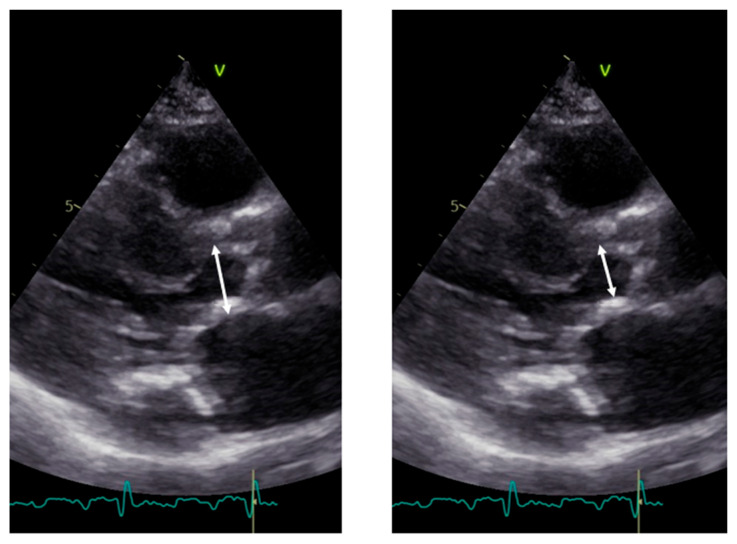

LVOT diameter. The accurate two-dimensional (2D) measurement of LVOT is crucial when assessing AS, as it represents a significant potential source of error in calculating the aortic valve area (AVA) using the continuity equation [15,16,17]. The LVOT measurement is squared within the continuity equation, so any small error in measurement is significantly amplified [18,19]. LVOT diameter should be measured in mid-systole [20]. Mid-systole is the point of the cardiac cycle when the shape of the aortic annulus becomes most circular, and its area becomes maximal. However, for the LVOT, there is no evidence of shape variation from oval to circular throughout systole. Nonetheless, mid-systole should be identified as the frame at half of the total number of frames available between the aortic opening and closure. In this mid-systolic frame, LVOT is measured from the inner edge to the inner edge of the septal endocardium to the anterior mitral leaflet, parallel to the plane of the aortic valve [20]. If a long-axis view is not available, it is not recommended to measure the LVOT from apical views. It is important to recognize that during image acquisition, the parasternal long-axis view provides better axial resolution, whereas the LVOT apical view relies on lateral resolution, which is a limiting factor. It is important to recognize that after the identification of a correct long axis, imaging resolution improvement is fundamental. Axial resolution, as said before, is the most precise of the other two resolutions, lateral and elevational. Thus, quantitative measurements are made most reliably using data derived from a perpendicular alignment. In order to improve axial resolution, higher frequencies should be used. In addition, harmonic imaging is always recommended in that it improves endocardial definition [21]. Gain controls, which adjust the displayed amplitude of the received signals, should be corrected because excessive gain settings can cause “blooming” of the echoes (Figure 3, left panel), leading to a significant underestimation of the LVOT diameter. Conversely, by lowering too much, the gain prevents proper visualization of the anterior endocardium, resulting in an overestimation of the LVOT diameter (Figure 3, right panel).

Figure 3.

Over gain (left panel) and lower gain (right panel) in the long-axis view along the same patient.